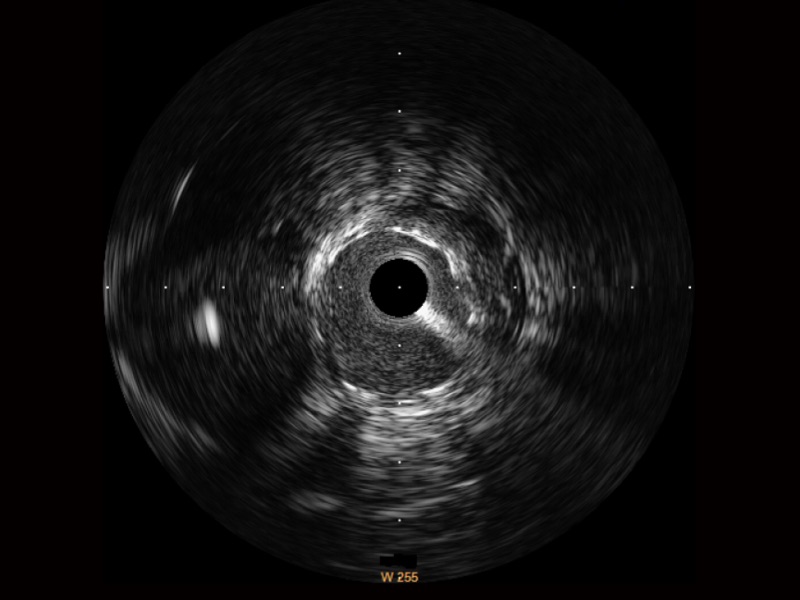

传统IVUS图像

对比传统IVUS导管成像,九州酷游宽频IVUS图像的近场支架梁显影更细腻,远场中膜外血管仍清晰可辨,兼顾远中近,兼顾分辨力与穿透深度